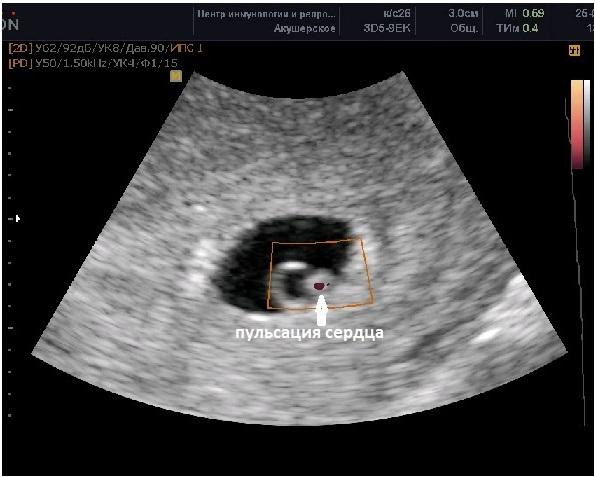

Внутри плодного яйца уже заметно «колечко с драгоценным камнем», которое обозначает желточный мешок и заметный эмбрион. Сердцебиение эмбриона начинает фиксироваться в начале 6-й акушерской недели. Наличие пульсации сердца считается надежным признаком успешного продолжения беременности.

Если при КТР ≥6 мм пульсация сердца отсутствует, то можно говорить об остановке развития эмбриона. Нормальная частота сердечных сокращений на начальном этапе 6-й недели составляет 70-90 ударов в минуту, но к концу недели эта цифра превышает 100 ударов. Наличие одного желточного мешка, одного эмбриона и пульсирующего сердца в большинстве случаев свидетельствует об одноплодной беременности.

СВД плодного яйца за этот период колеблется от 13 до 23 мм, а КТР эмбриона составляет 4-9 мм.